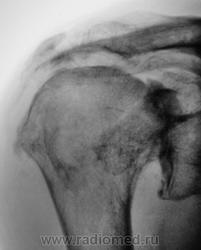

Пациент направлен на рентгенографию плечевого сустава хирургом.

При обращении пациент предъявляет жалобы на боли в плечевом суставе. Хирург поликлиники пациента не осматривал, а сразу соорудил направление на рентгенологическое исследование.

В левом суставе - вероятно изменения за счёт артроза, обызвествления связок

Двусторонний деформирующий остеоартроз: справа усилен верхним подвывихом с образованием неартроза с акромиальным отростком.

2-сторонний ДОА, справа подвывих, неоартроз + калькулезный (известковый) бурсит(возможно тоже 2-сторонний)